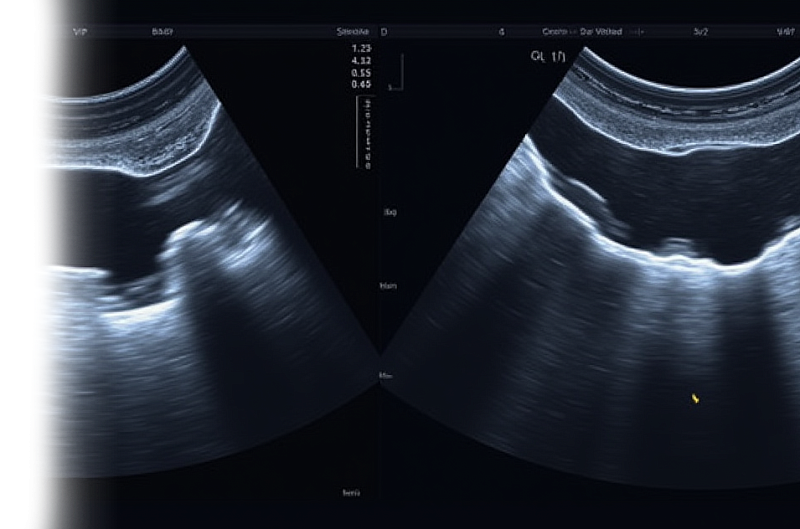

УЗИ сухожилий – высокоинформативный и неинвазивный метод исследования, который в режиме реального времени позволяет оценить структуру сухожилий.

Ультразвуковое исследование проводится в удобном для пациента положении, лежа на спине или сидя на кушетке. Исследуемую область нужно предварительно освободить от одежды и украшений. На кожу наносится специальный гель, после чего врач начинает оценку структуры сухожилия.